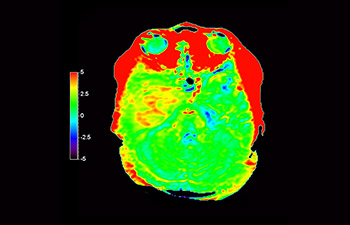

Astrocitoma

Astrocitoma cerebral, después de radioterapia

con 3D APT